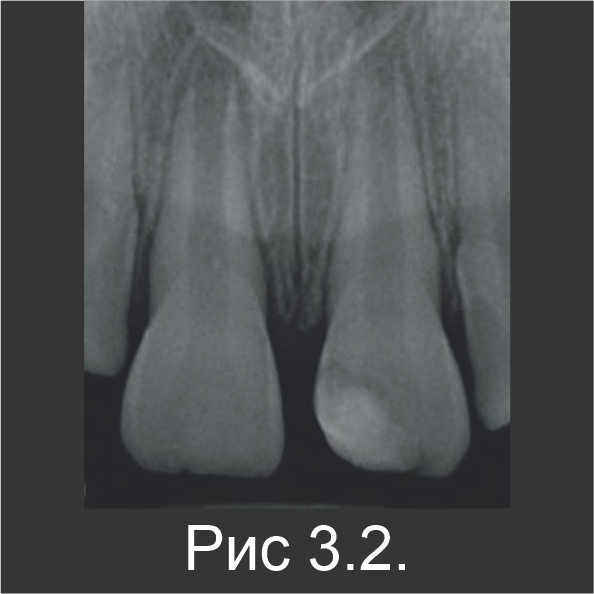

У 7-летнего мальчика произошел осложненный перелом коронки зуба 21. Это произошло во время занятий спортом (рис. 3.1). В зубе 21 наблюдалась чувствительность к перкуссии, а пульпа была открытой. Пациенту ввели местный анестетик, а участок перелома очистили промыванием физиологическим раствором. Непосредственно на открытую пульпу нанесли Biodentine™, который также оставили в качестве временной пломбы (рис. 3.2).